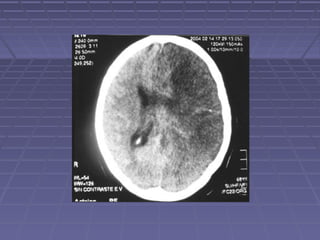

 TAC de cráneoTAC de cráneo si: persisten o aumentan lassi: persisten o aumentan las

manifestaciones clínicas, se sospechamanifestaciones clínicas, se sospecha

herniación, persiste la fiebre.herniación, persiste la fiebre.

 TC: hidrocefalia, lesiones vasculares,TC: hidrocefalia, lesiones vasculares,

tuberculomastuberculomas